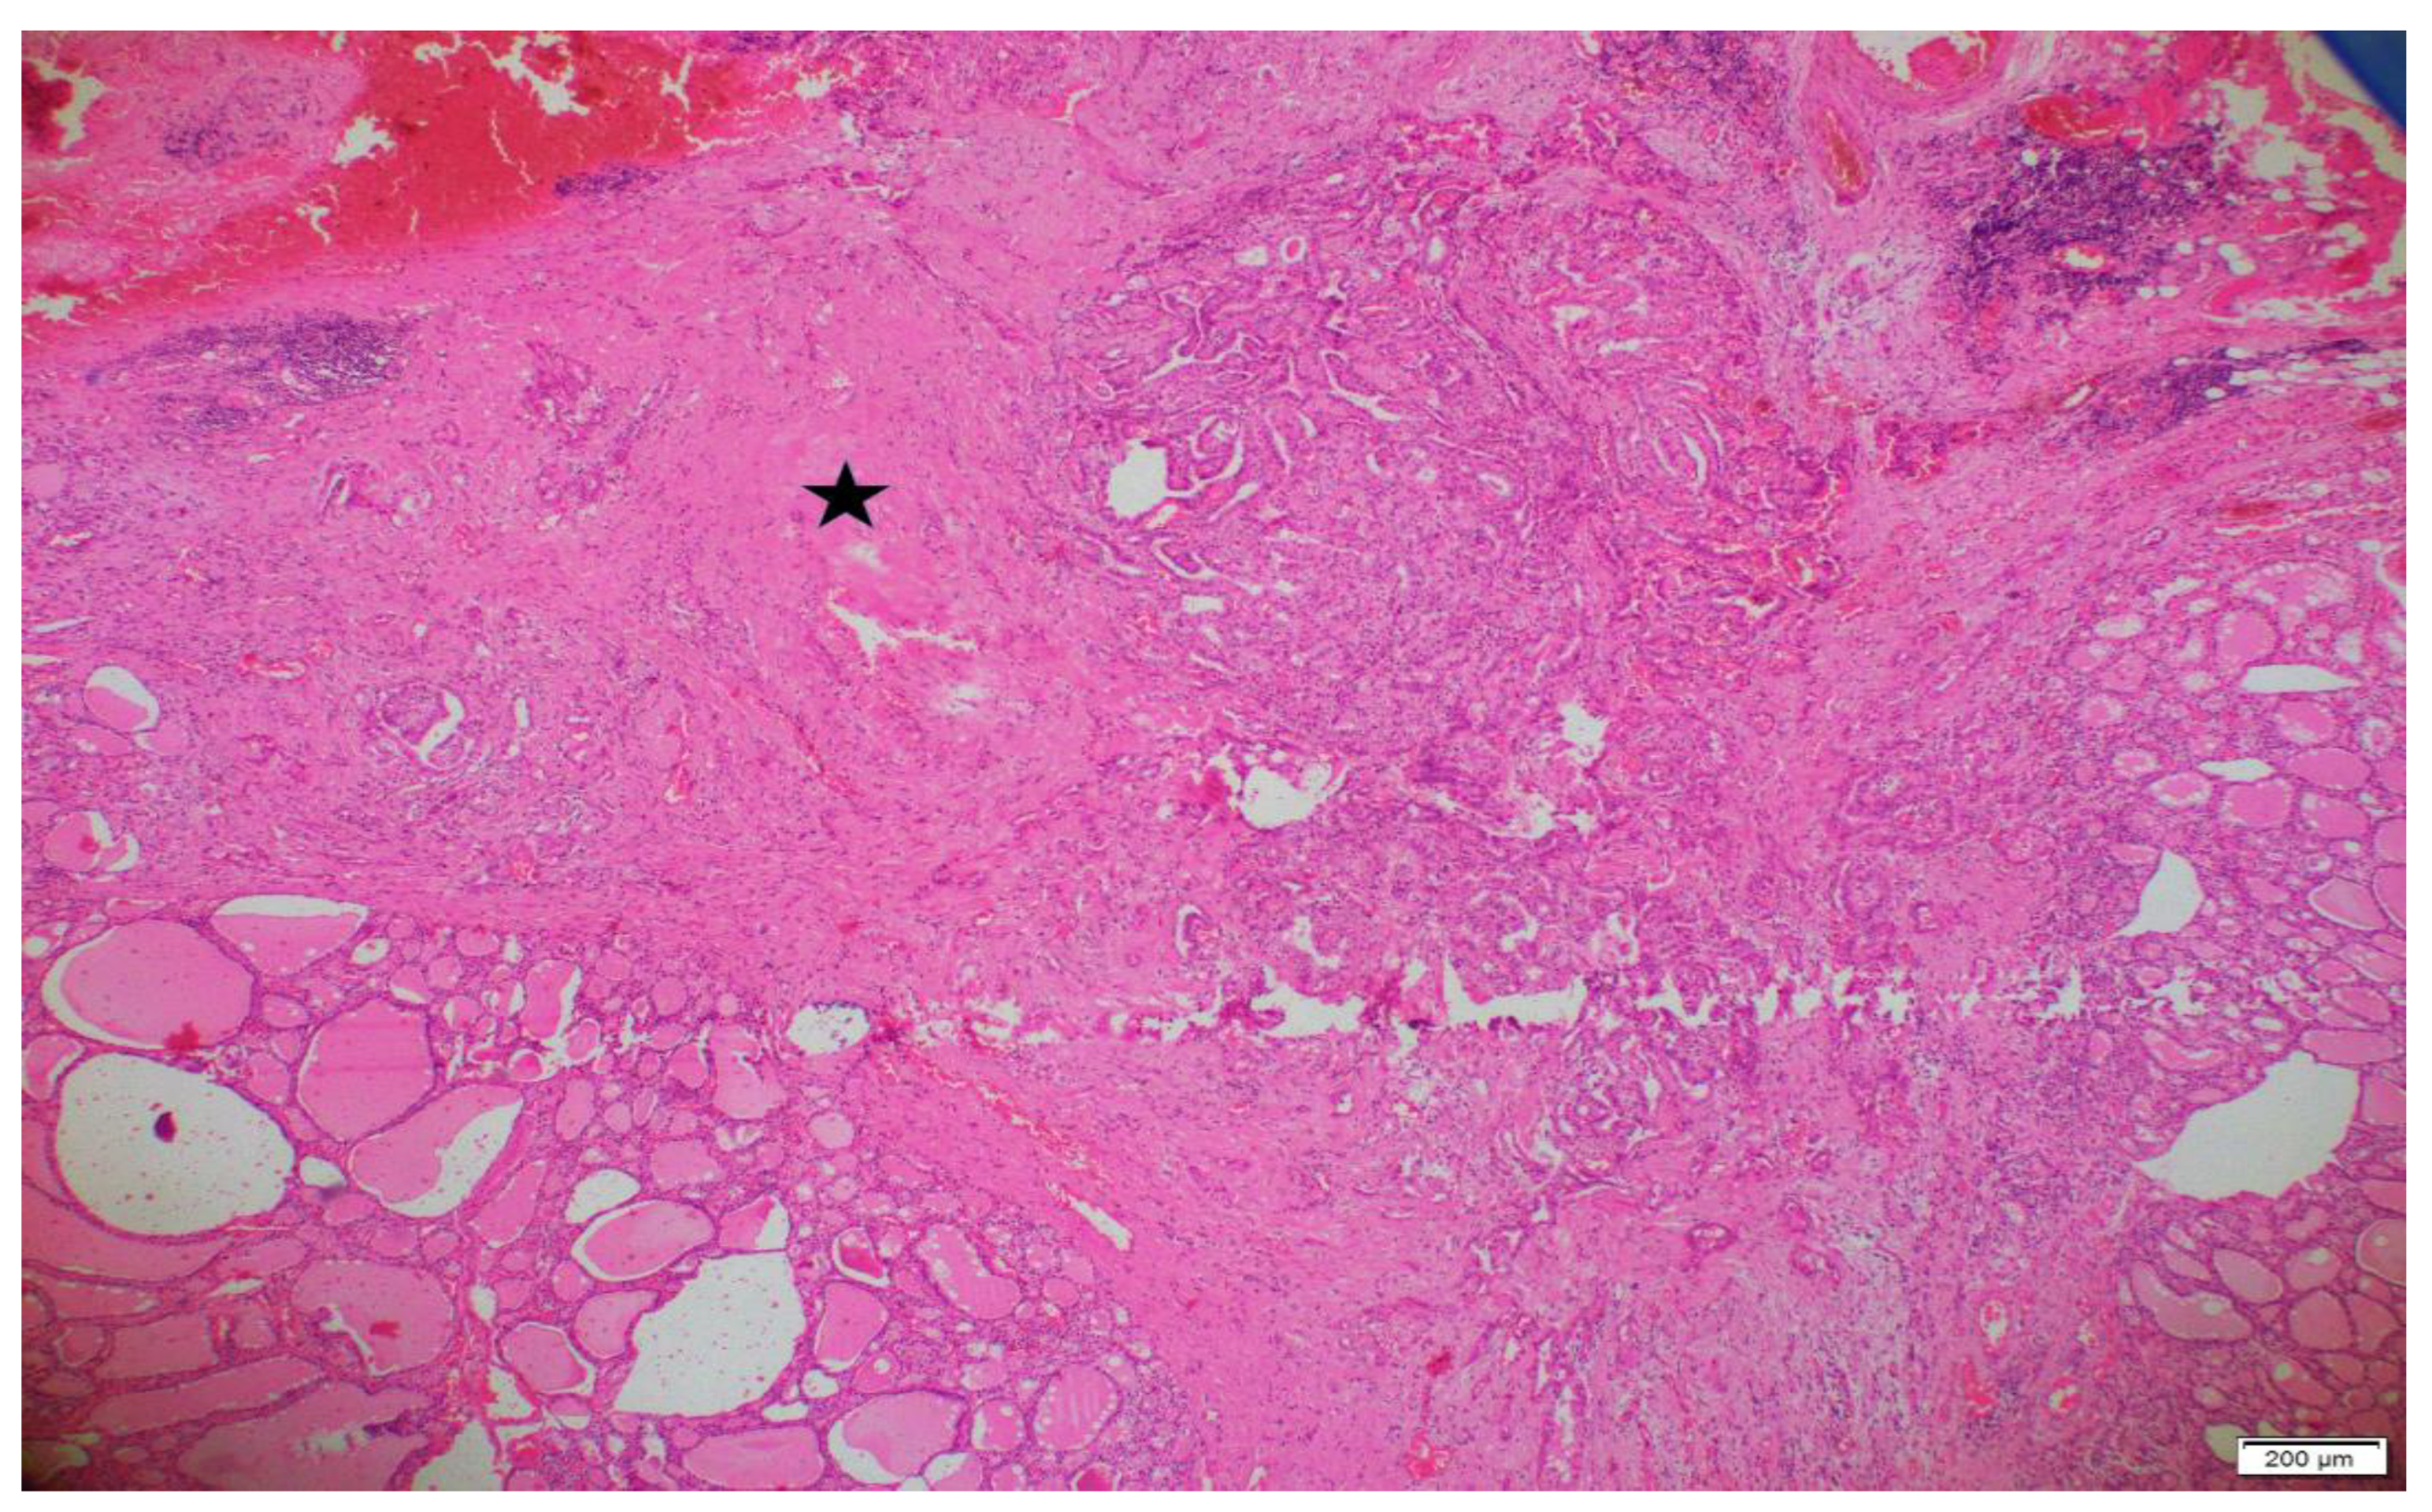

Pathology archive slides of surgical specimens were reviewed by a pathologist, blindly. Patients were divided according to the tumor subtypes, age, gender, diameter of the tumor, capsular invasion, lymphovascular invasion (LVI), perineural invasion, lymph node metastases, multifocality and surgical margins. IF was determined as unorganized collagenous thickening around or in the tumor, which was not relevant, with a capsule formation. An example of IF is represented in Figure 1. While examining IF, hemorrhagic and fibrotic foci due to preoperative FNAB were determined by localization and period of time between interventions, and were excluded.

Figure 1. An area of interstitial fibrosis in and around a classic variant papillary microcarcinoma (×40 magnification). The pentagram (*) indicates the region of interstitial fibrosis.